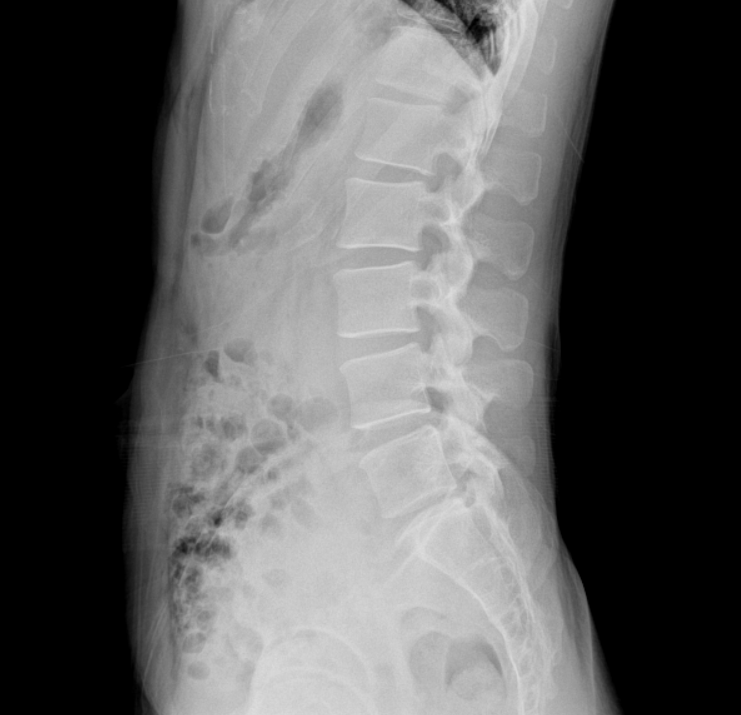

실제로 심한 염좌를 두차례나 겪고 한의원에서까지 그런 말을 하니 이전에 신경외과 소견은 어떻게 이해해야하는지 궁금합니다. 그리고 실제로 제가 스스로 허리를 만져보면 조금만 숙여도 뼈가 심각하게 튀어나오는데.. 이건 큰 문제 없는건지 궁금합니다. 엑스레이상에도 거의 가죽에 붙어있는것 같은데.. 이것은 문제가 없을까요?

글쎄요 특별한 이상이 없어보입니다. 뼈가 피부에 가까이 있어도 상관없습니다.한의사 선생님 의견은 제가 감히 드릴 말씀이 없습니다

현재 엑스레이에서는 문제가 없습니다. 허리 통증을 유발하는 것은 인대나 힘줄, 디스크 등의 손상이나 염증으로 치료를 하면서 증상이 호전되면 운동을 하시는 것이 필요하겠습니다.